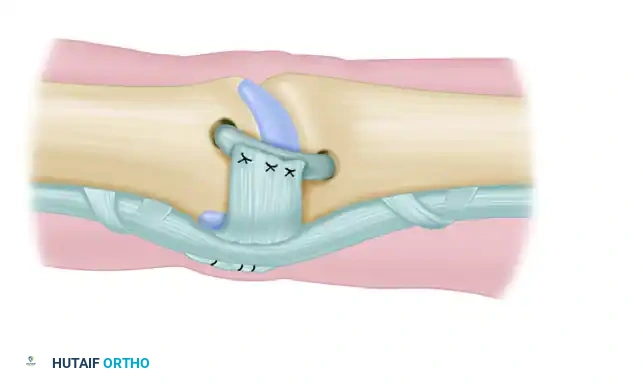

Diagrammatic representation of the reconstruction of the collateral ligament of the proximal interphalangeal joint with a tendon graft. The graft is passed through the transosseous tunnels.

- Button Fixation: Pass each wire loop (or suture ends) on the exiting ends of the graft through a piece of sterile felt (to protect the skin) and then through separate holes in a single sterile button resting on the contralateral intact skin.

- Tensioning: Pull the graft snug to eliminate laxity. Assess the joint for stability and ensure there is no impingement during a trial range of motion. Once optimal tension is achieved, tie the two wires (or sutures) together securely over the button.

6. Creation of an Accessory Collateral Ligament (Optional but Recommended)

To restore the volar stability provided by the accessory collateral ligament and prevent hyperextension:

* Flexor Sheath Utilization: An accessory collateral ligament may be created if necessary. Section a portion of the flexor tendon sheath (typically the A3 pulley or adjacent cruciform tissue) on the side opposite the defect.

* Transposition: Maintain its insertion into the bone on the side of the involved collateral ligament, and fold this fascia-like sheath over the newly grafted tendon.

* Suturing: Suture this sheath tissue to the graft with the finger held in full extension to ensure appropriate tensioning of the volar structures.

Creation of an accessory collateral ligament utilizing a portion of the flexor sheath folded over and sutured to the primary tendon graft.